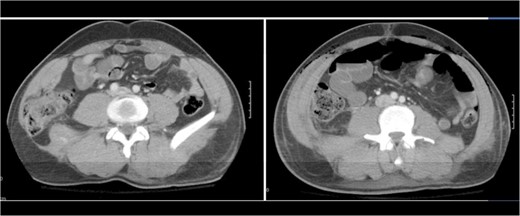

A 43-year-old male patient presented with a right-sided traumatic lumbar hernia after a blunt mechanism. The patient had been pinned between a dirt-mover’s claw arm resulting in a crush mechanism. He sustained injuries to the lumbar spine, sacrum, abdominal wall and 12th rib. On presentation, he did not have clinical or radiographic evidence necessitating abdominal exploration and was observed in a monitored setting. Computed tomography imaging demonstrated a Grynfeltt defect with herniation of the ascending colon and cecum through an area defined by the 12th rib, quadratus lumborum and internal oblique (Figures 1 and 2). After several days of observation and recuperation, the patient continued to have significant pain overlying the hernia site. We electively brought him to the operating room on post-injury Day 4. A laparoscopic repair of the traumatic hernia was performed. Key operative steps included: (i) Wide exposure of the hernia defect via incision of the peritoneum and transversalis as well as mobilization of the ascending colon and duodenal sweep (Figures 3 and 4). (ii) Primary repair of the defect with intra-corporeal suturing of the oblique musculature (Figures 5 and 6). (iii) Placement of an underlay mesh with appropriate redundancy at least 4 cm in all directions around the defect and seating against the iliac crest (Figure 7). Post-operative imaging demonstrates obliteration of the hernia defect and restoration of the abdominal wall (Figures 8 and 9). The patient has recovered, returned to the work force and has no pain or bulge at the repair site 6 months after injury.

Step 1 begins with incision of the peritoneum overlying the hernia.